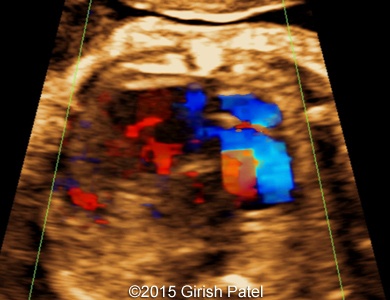

Following images and videos show a case of double inlet left ventricle with transposition of the great arteries that was seen at 26 and 36 weeks of otherwise non-complicated pregnancy.

Images 5, 6, 7: 2D color Doppler images showing the heart with double inlet left ventricle and transposition of the great arteries. Image 5 shows filling of the left ventricle via separate mitral and tricuspid valves (doubled red flow). Images 6 and 7 shows parallel arrangement of the aorta and pulmonary artery (blue flows).